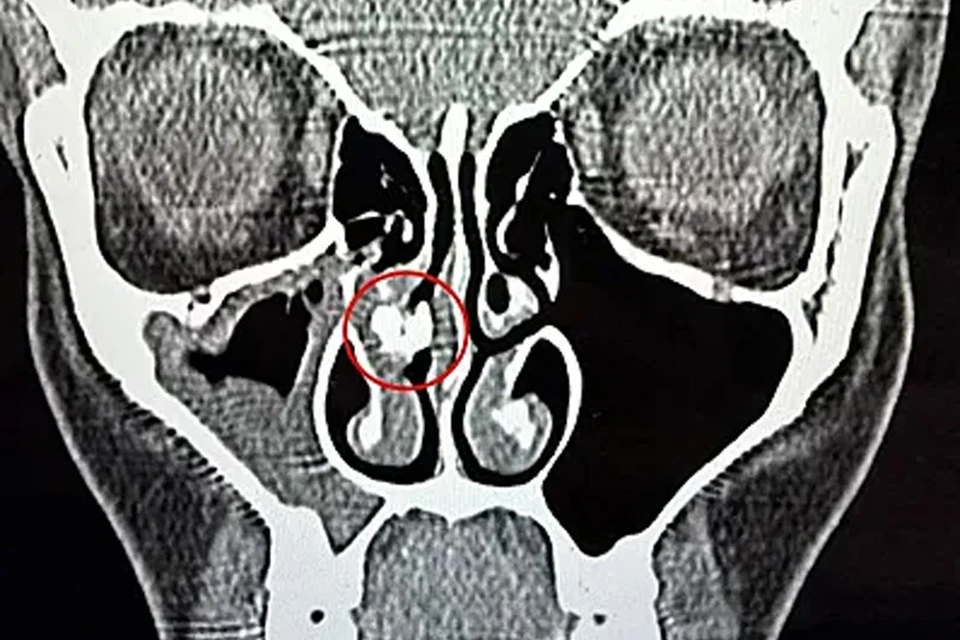

Переломным моментом стал 2025 год, когда женщина обратилась в больницу с синуситом. После компьютерной томографии врачи выявили в её носовой полости инородное тело. Спустя час его извлекли пинцетом — им оказался кусок клейкой ленты. Рейбо показала находку в TikTok и призналась, что не понимает, как скотч оказался в её носу и сколько времени он там находился.